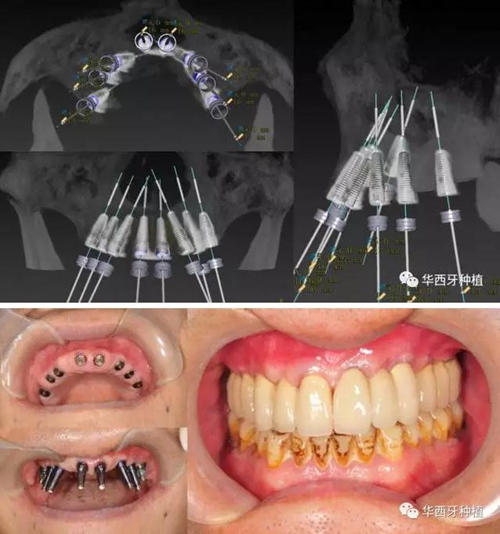

吳教授提到了使用數(shù)字化建模與導板的聯(lián)合應用,不僅可以從設計上降低修復難度,便于在修復為導向的設計中種植體方向的確定,同時可以加入微創(chuàng)的手術方法,減輕術中創(chuàng)傷。

吳教授特別針對手術難度更大的all-on-four修復做了詳細的關于概念、設計、操作、修復的描述,首先是針對難度最大的手術環(huán)節(jié),就解剖、微創(chuàng)操作分別加以闡述。將他自己在臨床工作中的寶貴經(jīng)驗分享給了大家。

對于傳統(tǒng)的all-on-four術式,吳教授加入了微創(chuàng)的指導思想,設計時同樣加入數(shù)字化三維重建與修復一體化設計,增加了手術的可控性,同時極大減輕了患者的創(chuàng)傷程度,縮短了修復周期。